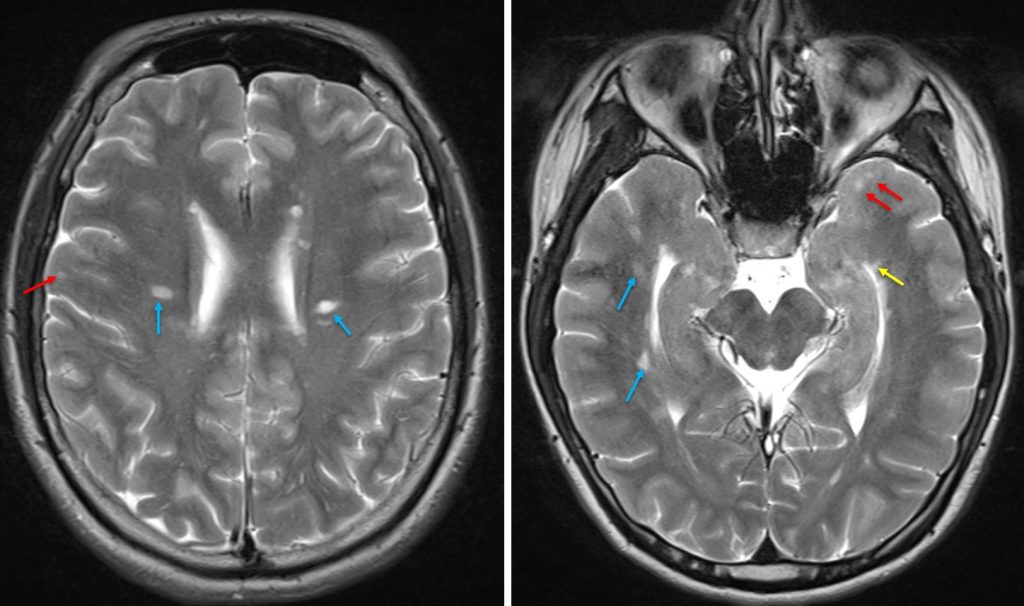

Dawson fingers (multiple sclerosis) Radiology Cases Fingers Locking Multiple Sclerosis Painful vision loss in one eye. Coping with curled fingers and hands. Claw hand can be congenital (present at birth) or. Vision problems can have many. Any condition that affects the nerves in the hand can cause your fingers to bend inward. What are the early signs of ms? The (curled) hand ms has dealt me has made it so. Fingers Locking Multiple Sclerosis.

Dawson's Finger in Multiple Sclerosis Fingers Locking Multiple Sclerosis This article will review what. What dawson’s fingers can reveal about multiple sclerosis. There are four potential early signs of ms that shouldn’t be ignored. At some point in the course of their disease, the majority of people with multiple sclerosis (ms) experience spasticity, a term. Why finger curl or claw hand occurs. Claw hand can be congenital (present at. Fingers Locking Multiple Sclerosis.

Dawson fingers (multiple sclerosis) Radiology Cases Fingers Locking Multiple Sclerosis Claw hand can be congenital (present at birth) or. Why finger curl or claw hand occurs. Coping with curled fingers and hands. The (curled) hand ms has dealt me has made it so that the smallest tasks, like picking up my cell phone or even a fork, is. However, there are other neurological conditions that these lesions may indicate. At. Fingers Locking Multiple Sclerosis.